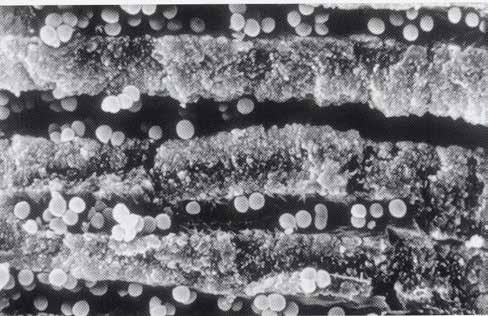

2. Kemomechanikai rendszerek Túlnyomásos rendszerek Alulnyomásos rendszerek

1. ábra: A 12. fog - a röntgenfelvételen nagyméretű periapikális elváltozás látható. A tünetmentes fogat ISO 25/.06 TF Adaptive reszelővel (Kerr Dental) preparáltuk. – 2. ábra: A 12. fog gyökércsatornájának tömését ásványi trioxid aggregátummal (ENDOSEAL MTA, Maruchi) végeztük. Figyeljük meg az apikális elágazás lezárását, ami az apikális terminus hatékony tisztítása és dekontaminálása miatt lehetséges. A gyógyulás 12 hónap elteltével csaknem teljes volt. – 3. ábra: 33. fog - a páciensnél egy bukkális sinus traktus volt látható, amely röntgenfelvételen a 32. és a 33. fog közötti területnek felelt meg. A CBCT és a röntgenfelvétel nagyméretű periradikuláris elváltozást mutatott, különösen a disztális oldalon. A preparálást 20/,07v ProTaper Gold (F1; Dentsply Sirona) készülékkel végeztük. – 4. ábra: A 33. fog gyökércsatorna obturációját sealer és hordozó alapú guttapercha (AH Plus és Thermafil, Dentsply Sirona) segítségével végeztük. A hat hónappal a műtét után végzett röntgenellenőrzés azt mutatta, hogy több oldalsó csatorna feltöltődött, és a gyógyulási folyamat folyamatban van.

keletkeznek [25-29]. A másodlagos kavitációs buborékok összeomlásuk során a csatornafalak közvetlen közelében vannak, nyírófeszültséget és örvényes áramlásokat generálva, amelyek képesek eltávolítani a törmeléket, a kenetréteget és a biofilmet a gyökércsatorna felszínéről, valamint a fel nem fedezett és műszerrel nem rendelkező anatómiai területekről, például az isztmuszokból, az oldalsó csatornákból, a hurkokból és a ramifikációkból, ezáltal tovább fokozva a tisztítási és dekontaminációs mechanizmust (1-4. ábra). A gyökércsatorna mentén létrejövő fokozott nyomás következésképpen az irrigálószereknek a dentinális tubulusokba való behatolásának mélységét is növeli [25-28].